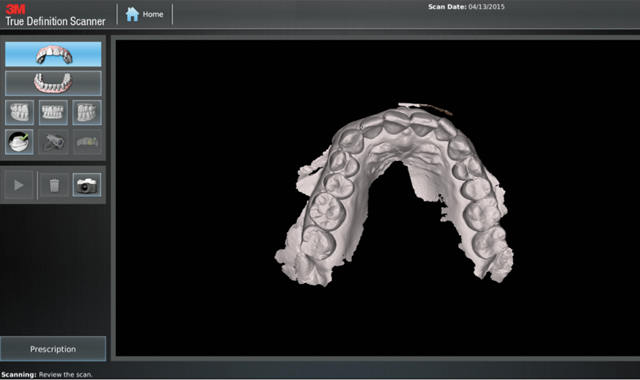

I also utilize digital impressions with the 3M™ True Definition Scanner, which provides many benefits leading to faster, easier and better outcomes.

In my practice we use the True Definition scanner for initial Invisalign treatment, mid-course corrections, refinements and Vivera® retainers. It’s a simple process using digital impressions: just complete the True Definition scanner prescription to send the scans

Fig. 1

to Align, and then complete the Invisalign prescription with the uploaded scans. The following case illustrates the many benefits of using the True Definition scanner with Invisalign.

We scanned the upper and lower arches capturing all incisal edges, occlusal surfaces, interproximal embrasures, distals of terminal molars and 3 mm of gingival margins (Figs. 4-7). There was no need to scan the bite. We submitted the scans to Align by completing the prescription on the True Definition scanner (Fig. 8).